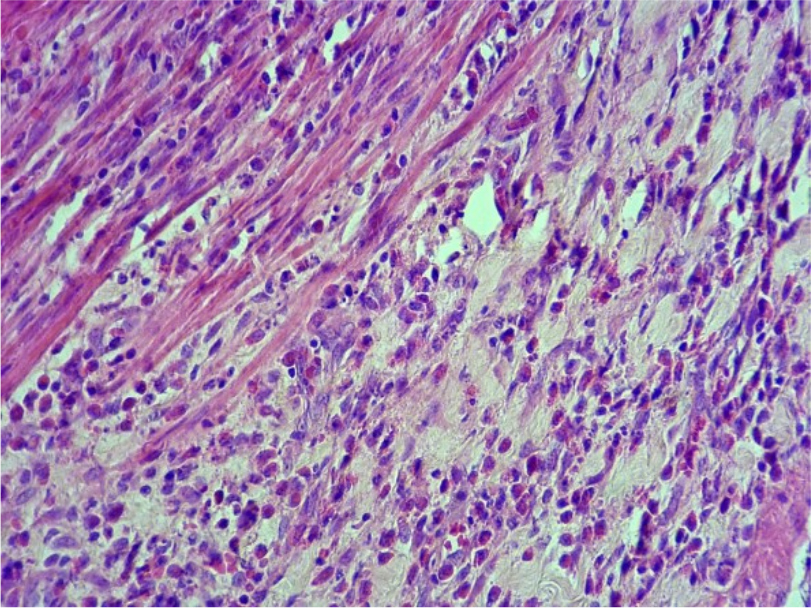

Результаты исследований. При проведении патоморфологического исследования у 10-ти животных из первой группы на 3-й день было выявлено слущивание эпителия слизистой оболочки желудка (Рис.1, 3), расширение просвета желез, очаговая атрофия экзокриноцитов (Рис. 2), на дне желез, часть париетальных экзокриноцитов в состоянии дистрофии с некробиозом – вакуолизацией цитоплазмы, кариопикнозом, границы клеток стерты, гомогенизированы. Васкуляризация стенки желудка активная, крупные сосуды гиперемированы, в подслизистой основе присутствуют единичные эозинофилы.

Рис.1. Слущивание эпителия слизистой оболочки стенки желудка. Ув. ×400

Рис. 2. Атрофия экзокриноцитов желез слизистой оболочки желудка. Ув. ×400

Изменения, обнаруженные в желудке у крыс 1 группы на 3-й день, свидетельствуют о дистрофии с некробиозом, кариопикнозе у части париетальных экзокриноцитов. Границы клеток стерты и гомогенезированы.